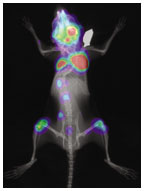

Modified bioluminescent cancer cells enable Kang to monitor metastatic tumors in living mice. (courtesy Yibin Kang)

Each form of cancer has a distinct pattern of metastasis, Kang says. Breast cancer commonly spreads to bones, lungs, lymph nodes, and the brain, for example, while colorectal cancer is most likely to spread to the liver. In Kang’s lab, researchers observe the process in real time, using living mice. The mice are injected with cancer cells that contain luciferase, the gene that makes fireflies glow. In the weeks and months after the cells are distributed through the bloodstream, they attack specific sites of the body and form tumors. Using a state-of-the-art machine that detects bioluminescence, Kang tracks a visible record of the location and size of the tumors to get a more precise idea of where and how metastasis occurs.

In Kang’s images of the mice, tumors are easy to see with minimal magnification, but the mechanisms behind metastasis operate on a much smaller scale, in the genes of cancer cells. Many researchers analyze tumors to search for a specific gene that is responsible for the way a given cancer spreads. With about 30,000 genes in the human genome, the one-gene approach seems tedious at best. “It’s also a biased approach,” Kang says, “because everybody wants to claim that their gene is the ‘magic bullet.’ ”